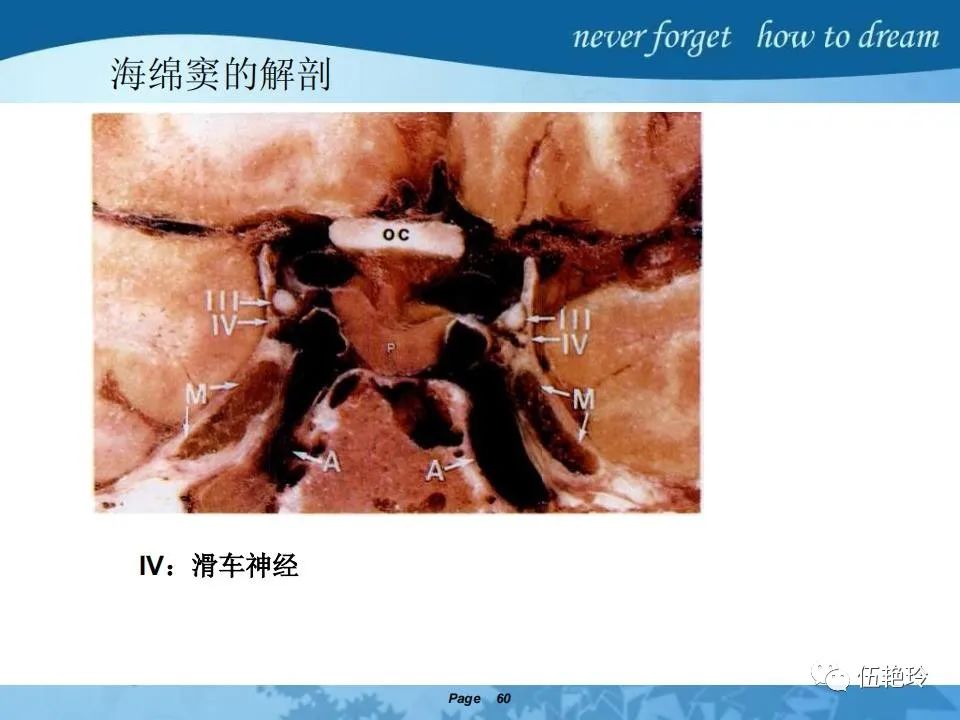

海绵窦区的解剖结构与鼻咽癌侵犯